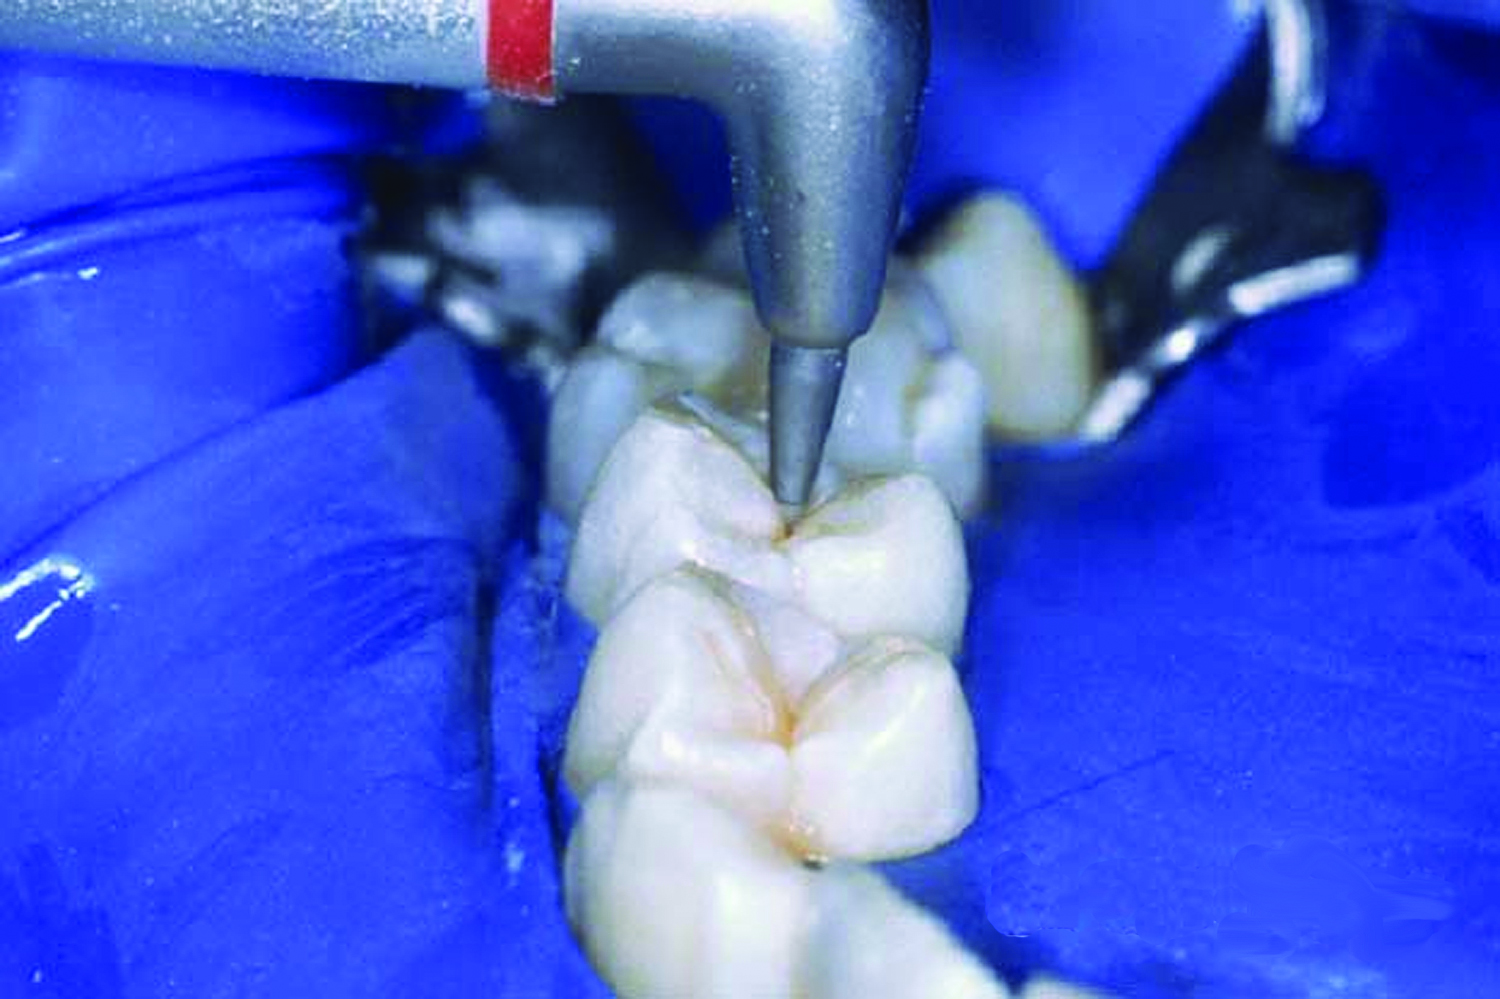

5. Apply phosphoric acid to the clean, dry surface for 15 to 60 seconds (Figure 8). The etching time varies; therefore, follow the manufacturer’s instructions. Liquid gel has a low viscosity, allowing good flow into the pits and fissures; however, it may be difficult to control. Gel etch is thick, and tinted for increased visibility and control, but may be more difficult to rinse off the tooth surface than a liquid gel.

Fig 8. Apply phosphoric acid to the clean, dry surface for 15 to 60 seconds.

Figure 8